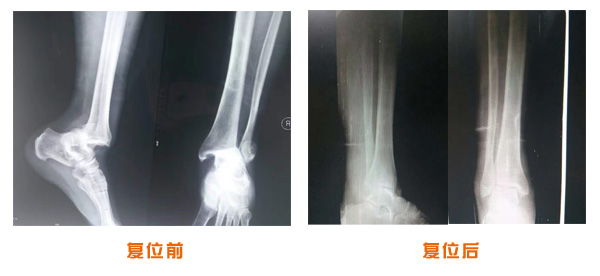

肥城市安駕莊梁氏骨科醫(yī)院是一所以梁氏手法正骨配合膏藥為特色的現(xiàn)代化專科醫(yī)院。